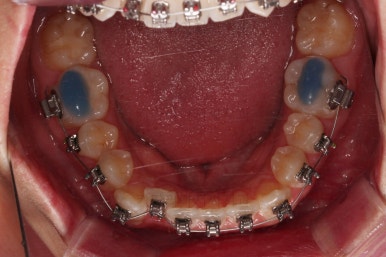

부산치아교정치과 초진 시 입안의 모습입니다.

앞니쪽이 위아래 모두 삐뚠 상태였고요.

왼쪽은 덧니로 툭 튀어나가 있고, 상대적으로 작은 앞니는 안으로 말려 들어가 아랫니와도 거꾸로 물리는 상태였습니다.

어금니도 물론 약간 삐뚤긴 하지만 앞니만큼 심한 상태는 아니었고 맞물리는 기능도 큰 불편함은 없으신 상태였습니다.